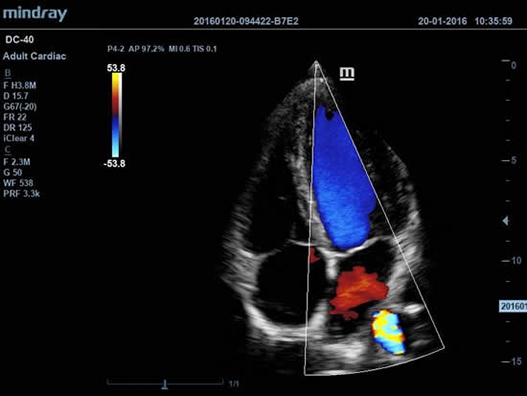

DC-40 имеет особое применение в кардиологической практике, благодаря функции Free Xros CM. Она позволяет отслеживать движения сердечной мышцы в различных фазах и одновременно определять синхронизацию миокарда. Это существенно повышает точность диагноза.

• Функции анатомического режима Free Xros M и Free Xros CM позволяют точно расчитывать анатомические параметры и отслеживать движения сердечной мышцы.

• Free Xros M™ - анатомический М-режим - это возможность вращения курсора в М-режиме под произвольным углом (при фиксированном положении датчика) и, соответственно, получения графика движения структур сердца в различных произвольных плоскостях;

• Free Xros CM™ - огибающий анатомический М-режим;

• Секторный фазированный датчик Mindray P4-2